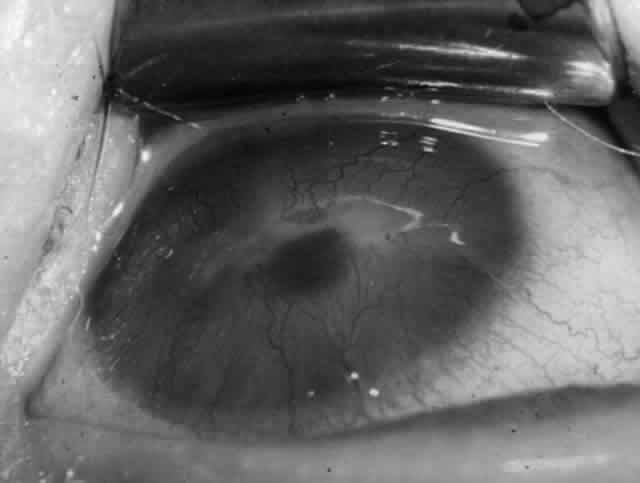

Clinically, the ocular disease in cicatricial pemphigoid (OCP) may present unilaterally in the form of a chronic, recurrent catarrhal conjunctivitis, but it eventually becomes bilateral. Subepithelial fibrosis is characteristic of stage 1 of OCP (Fig. 7). Stage 2 shows fornix foreshortening (Fig. 8), and symblepharon formation is the hallmark of stage 3 (Fig. 9). Stage 4, end-stage disease, is characterized by ankyloblepharon and surface keratinization (Fig. 10). Obstruction of the lacrimal ductules and meibomian gland ducts eventually produces an unstable tear film and progressive sicca syndrome, but it is to be emphasized that OCP is not a dry-eye syndrome until late in the disease course.20 Trichiasis and entropion occur because of the subepithelial fibrosis, with eventual keratopathy, corneal neovascularization, and corneal ulceration and scarring.20

Fig. 10. Stage 4 cicatricial pemphigoid. Progressive shrinkage of the conjunctiva resulted in extreme trichiasis and distichiasis and keratopathy, with compromise of meibomian ductules and lacrimal ductules and the production of a totally dry eye.